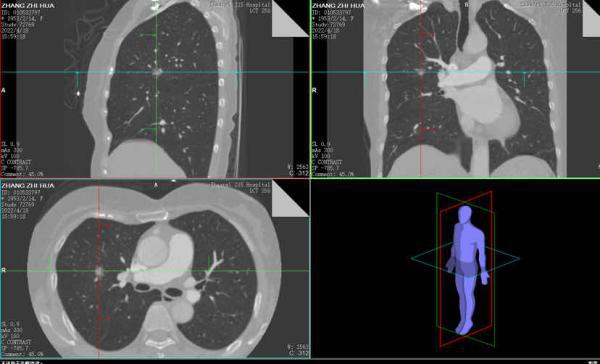

肺段切除术是肺结节及早期肺癌的重要治疗手段之一,精准的肺段手术是肿瘤学疗效和肺功能保护的前提,目标是在彻底切除病灶的同时最大程度地保留健康肺组织。胸外科团队通过专业软件对肺结节的位置进行了精确的定位,清晰显示出结节所处的肺段及靶段相关的支气管、血管情况。根据信息在术前进行详细的手术规划,确保了术中安全的、精准的切除靶肺段。